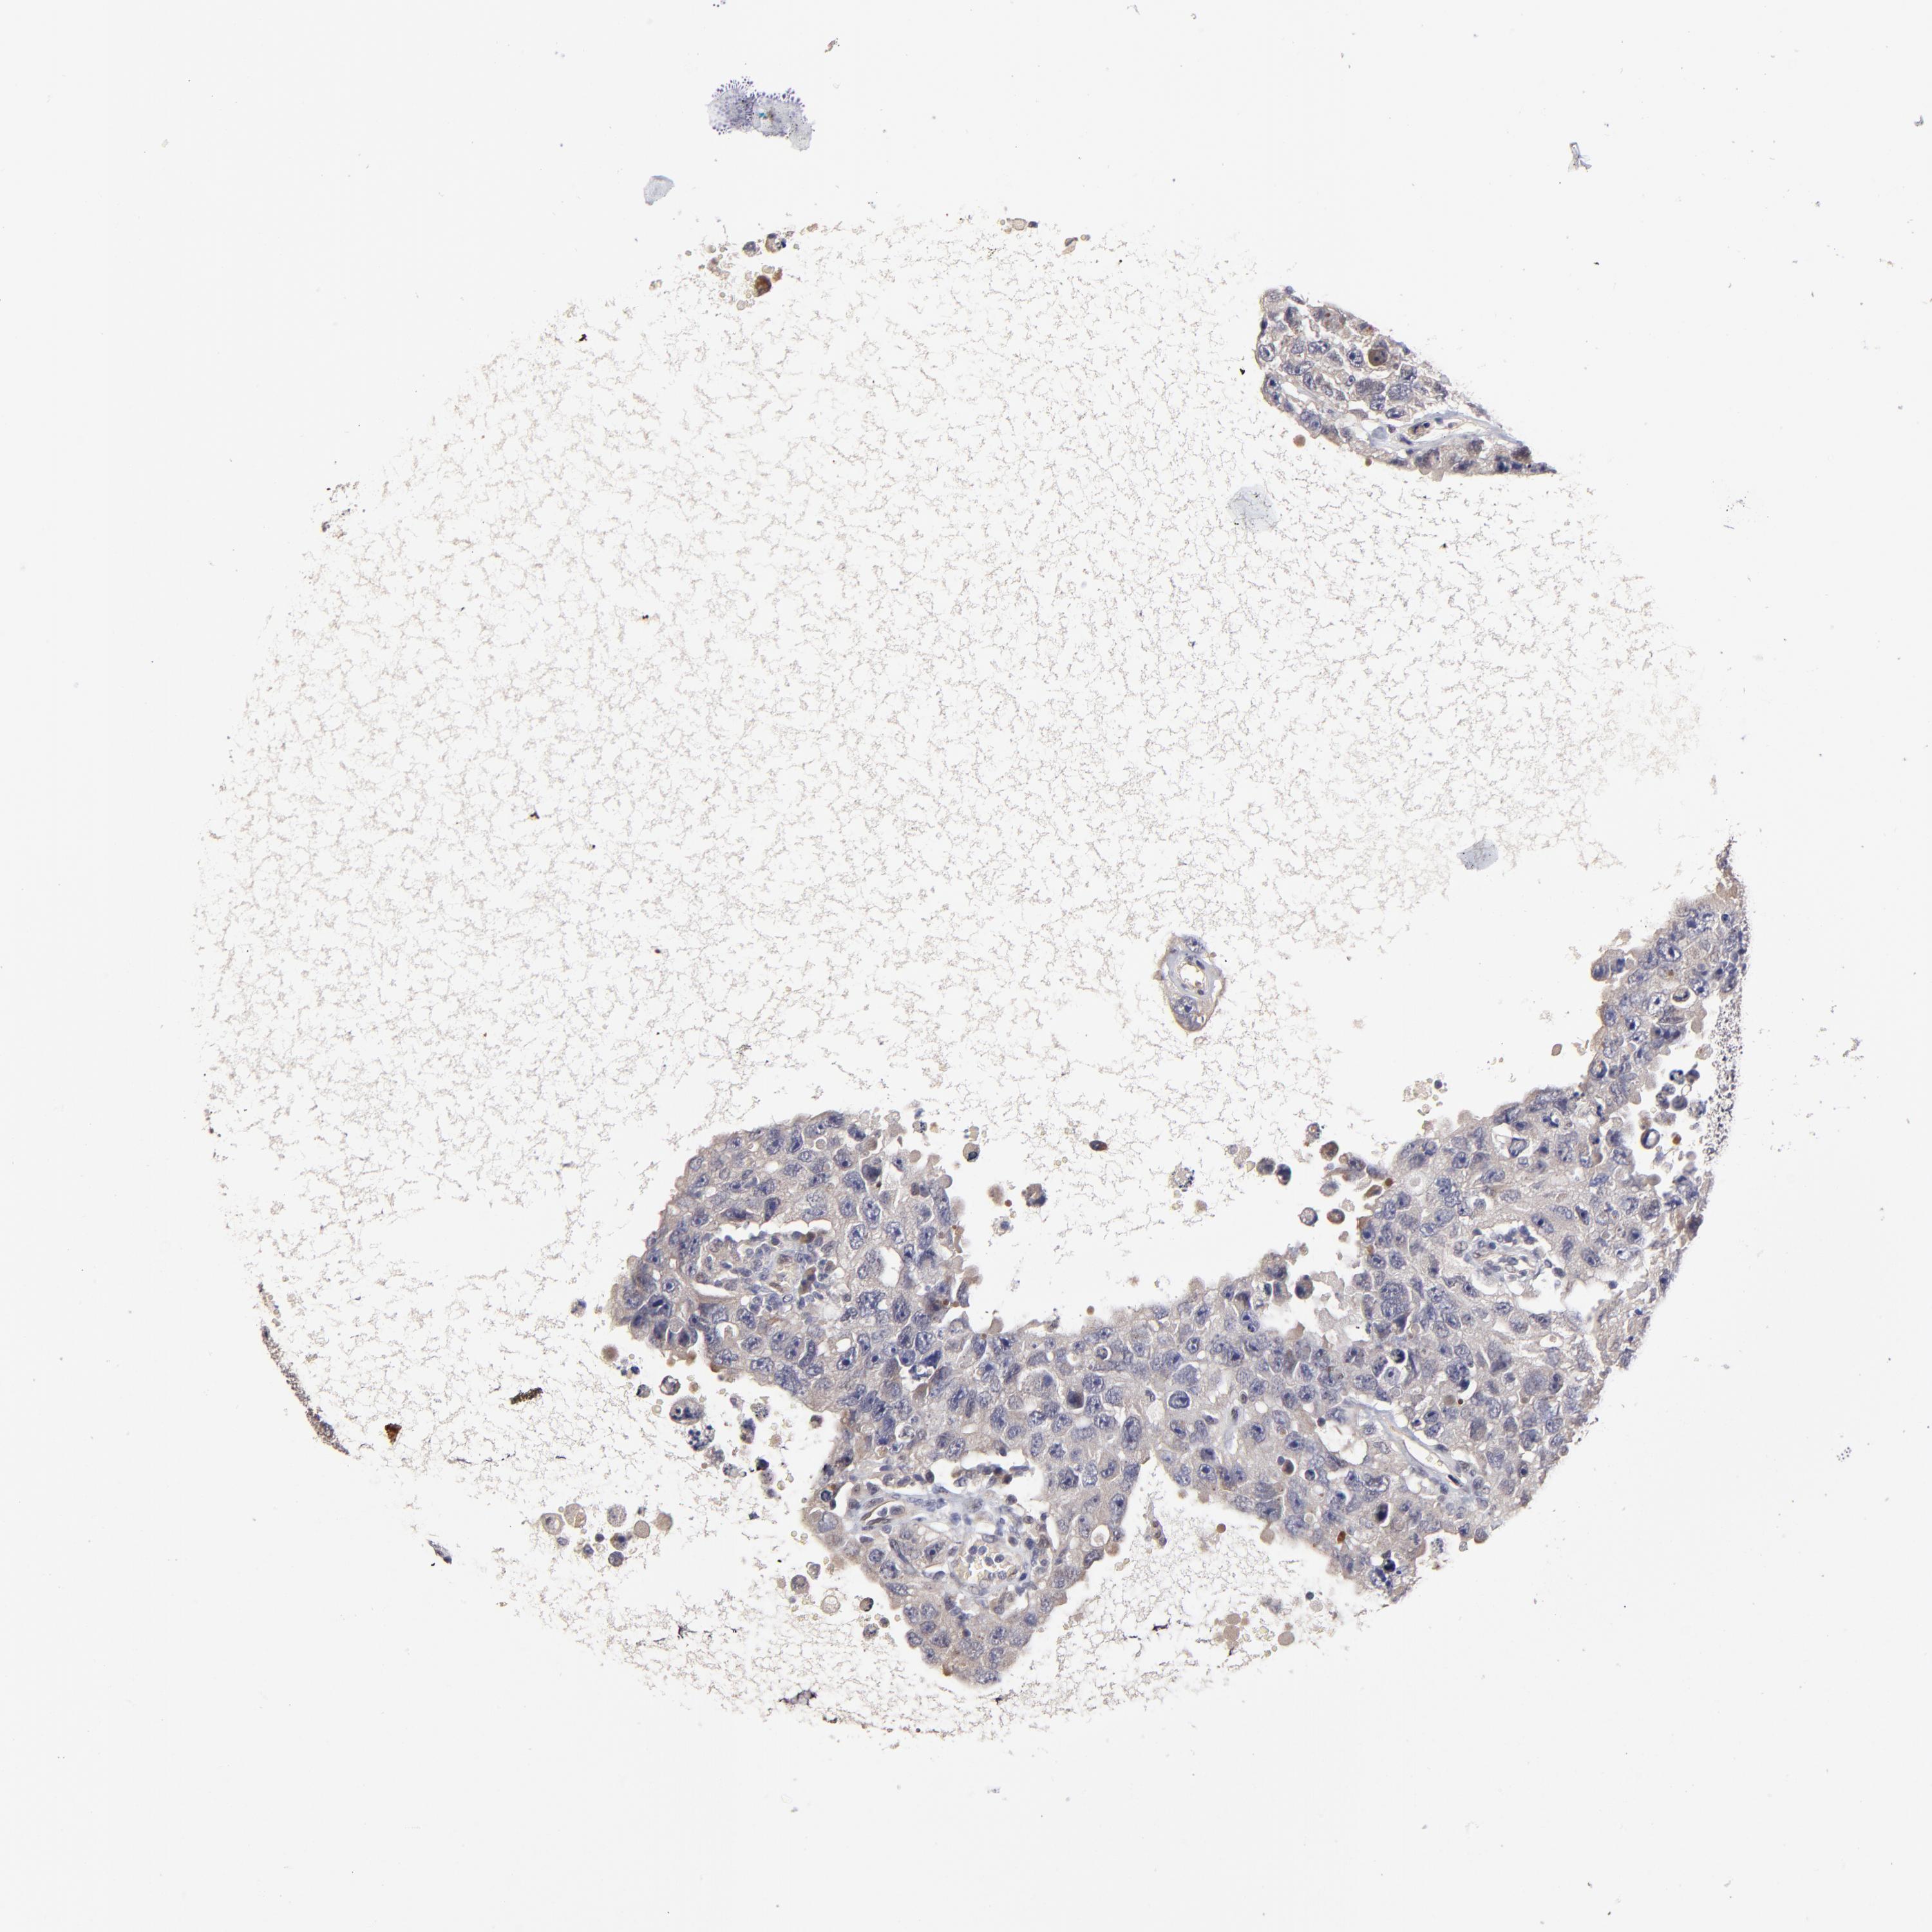

TESTIS CANCER - Protein expressioni

A mouse-over function shows sample information and annotation data. Click on an image to view it in a full screen mode. Samples can be filtered based on level of antibody staining by selecting one or several of the following categories: high, medium, low and not detected. The assay and annotation is described here.

Note that samples used for immunohistochemistry by the Human Protein Atlas do not correspond to samples in the TCGA dataset.

Antibody stainingi

Antibody staining in the annotated cell types in the current human tissue is reported as not detected, low, medium, or high, based on conventional immunohistochemistry profiling in selected tissues. This score is based on the combination of the staining intensity and fraction of stained cells.

Each image is clickable and will lead to virtual microscopy that enables deeper exploration of all samples and also displays staining intensity scores, fraction scores and subcellular localization as well as patient and tissue information for each sample.

Antibody HPA003204

Staining

High

Medium

Low

Not detected

Intensity

Strong

Moderate

Weak

Negative

Quantity

>75%

75%-25%

<25%

None

Location

Nuclear

Cytoplasmic/membranous

Cytoplasmic/membranous,nuclear

Carcinoma, Embryonal, NOS

Seminoma, NOS